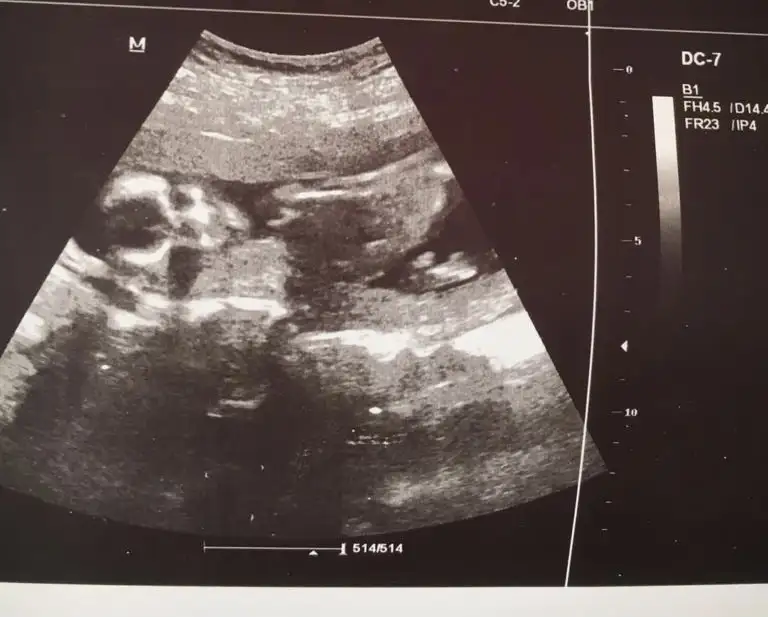

Ikra meyra Ikra meyra canim gecen sene kizimi tahminde dogru bilmistin 13+3haftalik tekrar gebeyim bi tahminde bulunurmusun bugun gittim devlette 16.haftaya kadar yasal olmadigi icin demiyorlarya dr al sen bak dedi verdi güldu🙃

Yaaa maşallah 🧿 kız gibi sanki emin olamadım